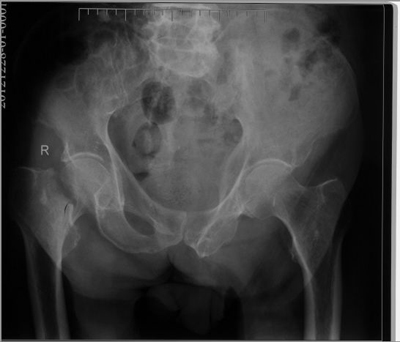

近日,我院骨一科成功为两位百岁超高龄老人施行了股骨颈骨折人工全髋关节置换术。患者术后均恢复良好,日前已康复出院并能拄拐行走。

100岁患者王某及94岁患者李某摔伤前生活均能自理。两位患者于家中活动时不慎跌倒致股骨颈骨折。其子女随即将老人送至我院骨一科就诊。入院后王坤正主任,党晓谦副主任,宋金辉副教授,张晨主治医师及唐一仑主治医师对患者进行了细致的体格检查,全身状态综合评估。同时邀请麻醉手术科、心内科、呼吸科等相关科室进行院内综合会诊,根据患者的年龄、病情及患者的全身状况,经过反复多次周密的讨论,决定施行全髋关节置换术。由于老人年岁均近“百岁”,手术风险极大,每个环节都有可能出现生命危险。为了使两位老人围手术期平稳安全度过,骨一科全体医护人员及麻醉手术科等相关科室均进行了充足的准备。

经过谨慎细致的术前准备,在麻醉手术科的全力配合下,由王坤正主任主刀,宋金辉副教授主助,张晨主治医师、唐一仑主治医师配合,先后为两位患者施行了股骨颈骨折人工全髋关节置换术。手术历时均约1个小时,过程安全平稳顺利。手术后患者生命体征平稳,经抗炎、镇痛、对症支持治疗患者逐步康复。术后1周,患者由家属搀扶拄拐下地活动。患者及其家属对手术效果非常满意。

股骨颈骨折是老年人较常见的骨折类型。老年人脏器机能代谢差,应激能力与功能低下,一旦发生股骨颈骨折,迫使患者卧床不起,易引起肺炎、褥疮、泌尿系感染、血管栓塞等并发症,严重者可引起死亡。传统的非手术治疗患者需长期卧床从而导致严重危及生命的并发症;故现在主张对能耐受手术的患者尽早行手术治疗,降低并发症的发生率,使患者早期活动,争取达到生活自理。